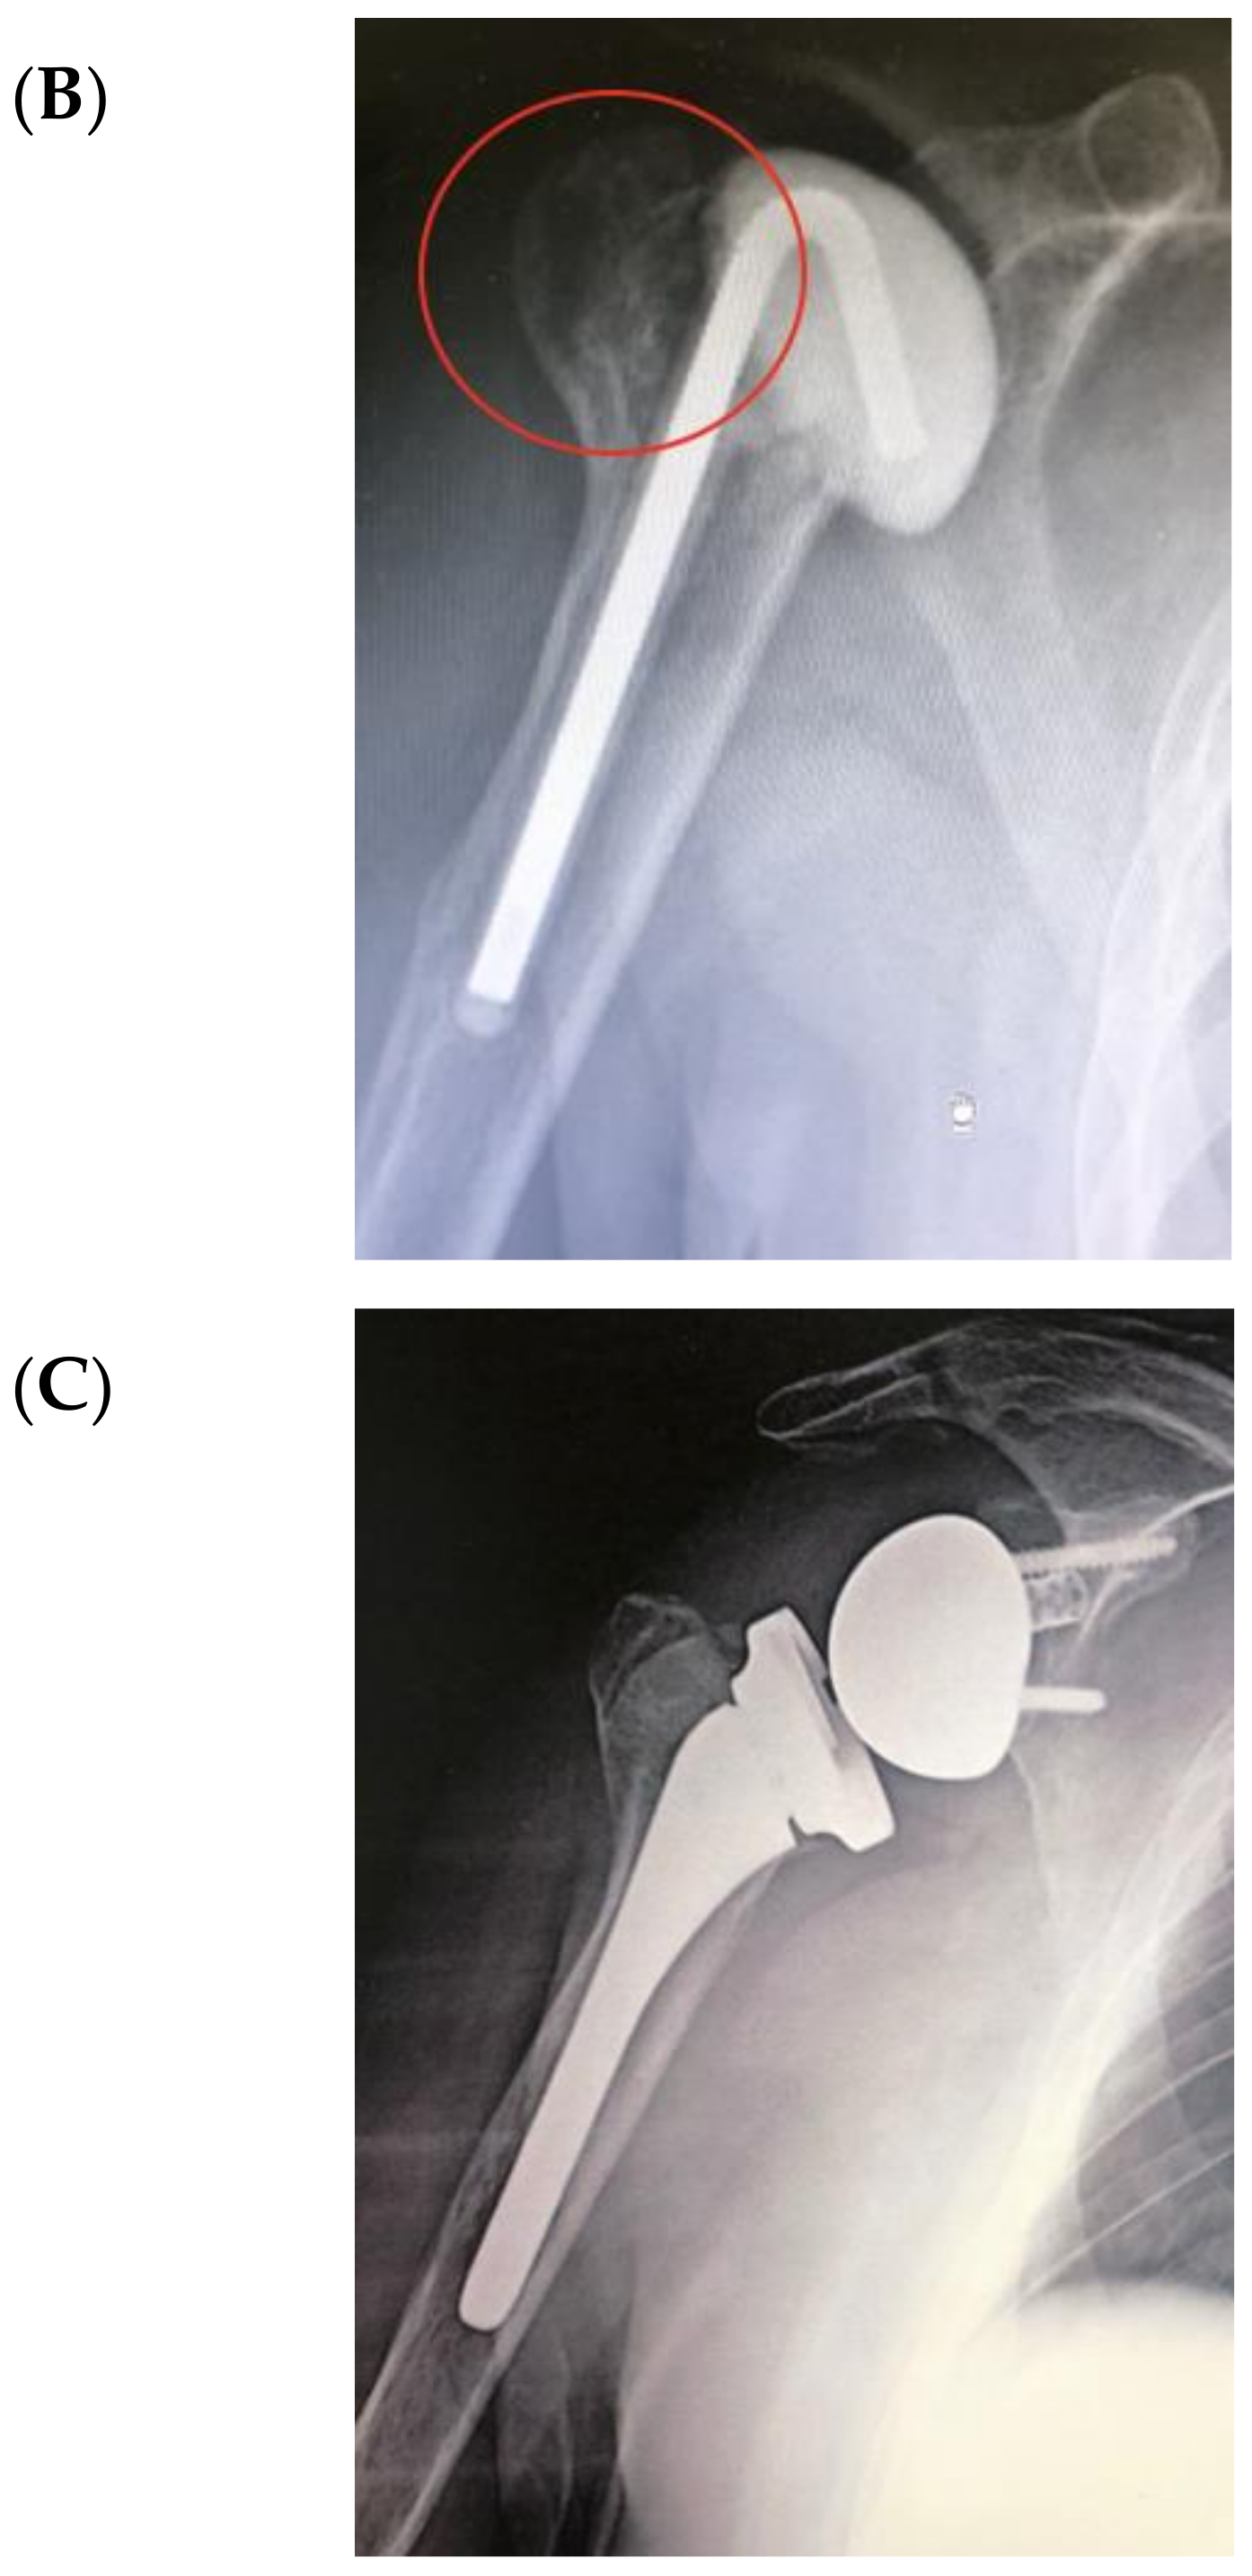

Figure 4 illustrates an infected case of proximal humerus fracture sequelae, originally treated with a plate, then treated according to our protocol. After plate removal, an RSA was implanted, which subsequently dislocated, resulting in infection. A two-stage procedure was performed: removal of the RSA, debridement, and implantation of a cement antibiotic spacer with vancomycin. MicroDTTect identified the pathogen (Cutibacterium acnes), intravenous antibiotics and infection eradication followed.

Figure 4.

(A) The X-ray of a case of an infected proximal humerus fracture sequelae, originally treated with a plate. (B) After plate removal, the first RSA was implanted, which subsequently dislocated, resulting in infection. (C) A two-stage procedure was performed: removal of the RSA, debridement and implant of a cement antibiotic spacer with vancomycin. (D) Spacer X-ray postoperative image.